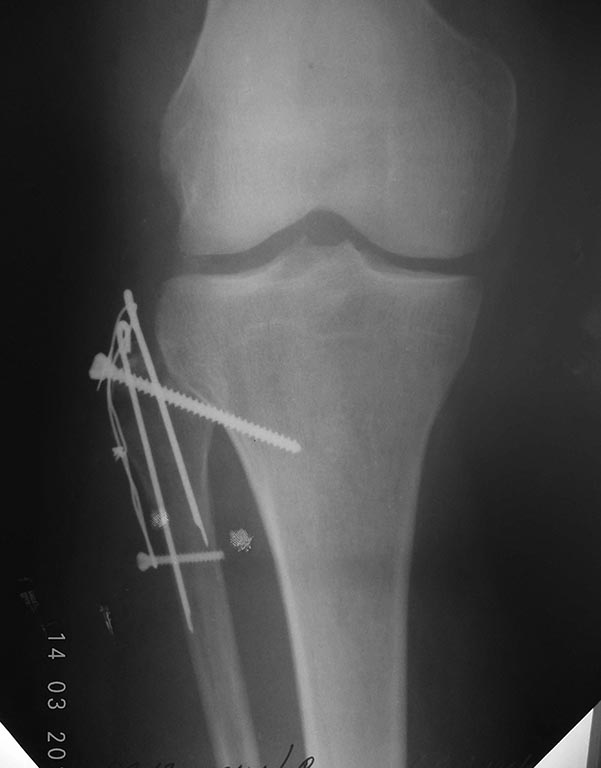

[Ortho] Перелом головки малоберцовой кости.

Вот результат. Явления неврит всё таки имеются.